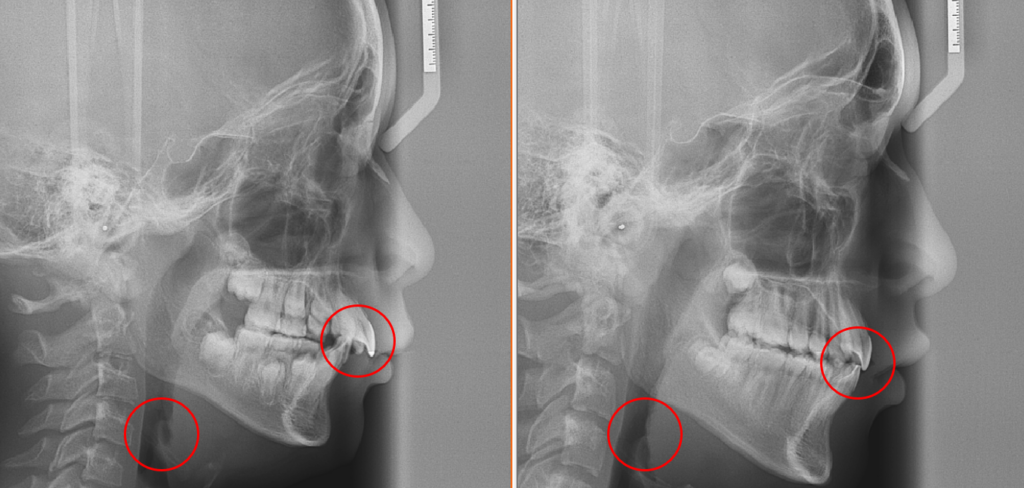

사진과 같이 올바른 혀의 위치이지만 의식 했을 때는 할 수 있으나 잠을 잘 때는 무의식중이기 때문에 쉽지가 않습니다.

사진과 같이 올바른 혀의 위치이지만 의식 했을 때는 할 수 있으나 잠을 잘 때는 무의식중이기 때문에 쉽지가 않습니다.

전 / 후

동그라미 표시 되어있는 곳을 보시면 Airway확장과 치아가 들어간게 보이실거에요. 착용만 잘해주신다면 좋은 효과를 이루어 낼 수 있어요.